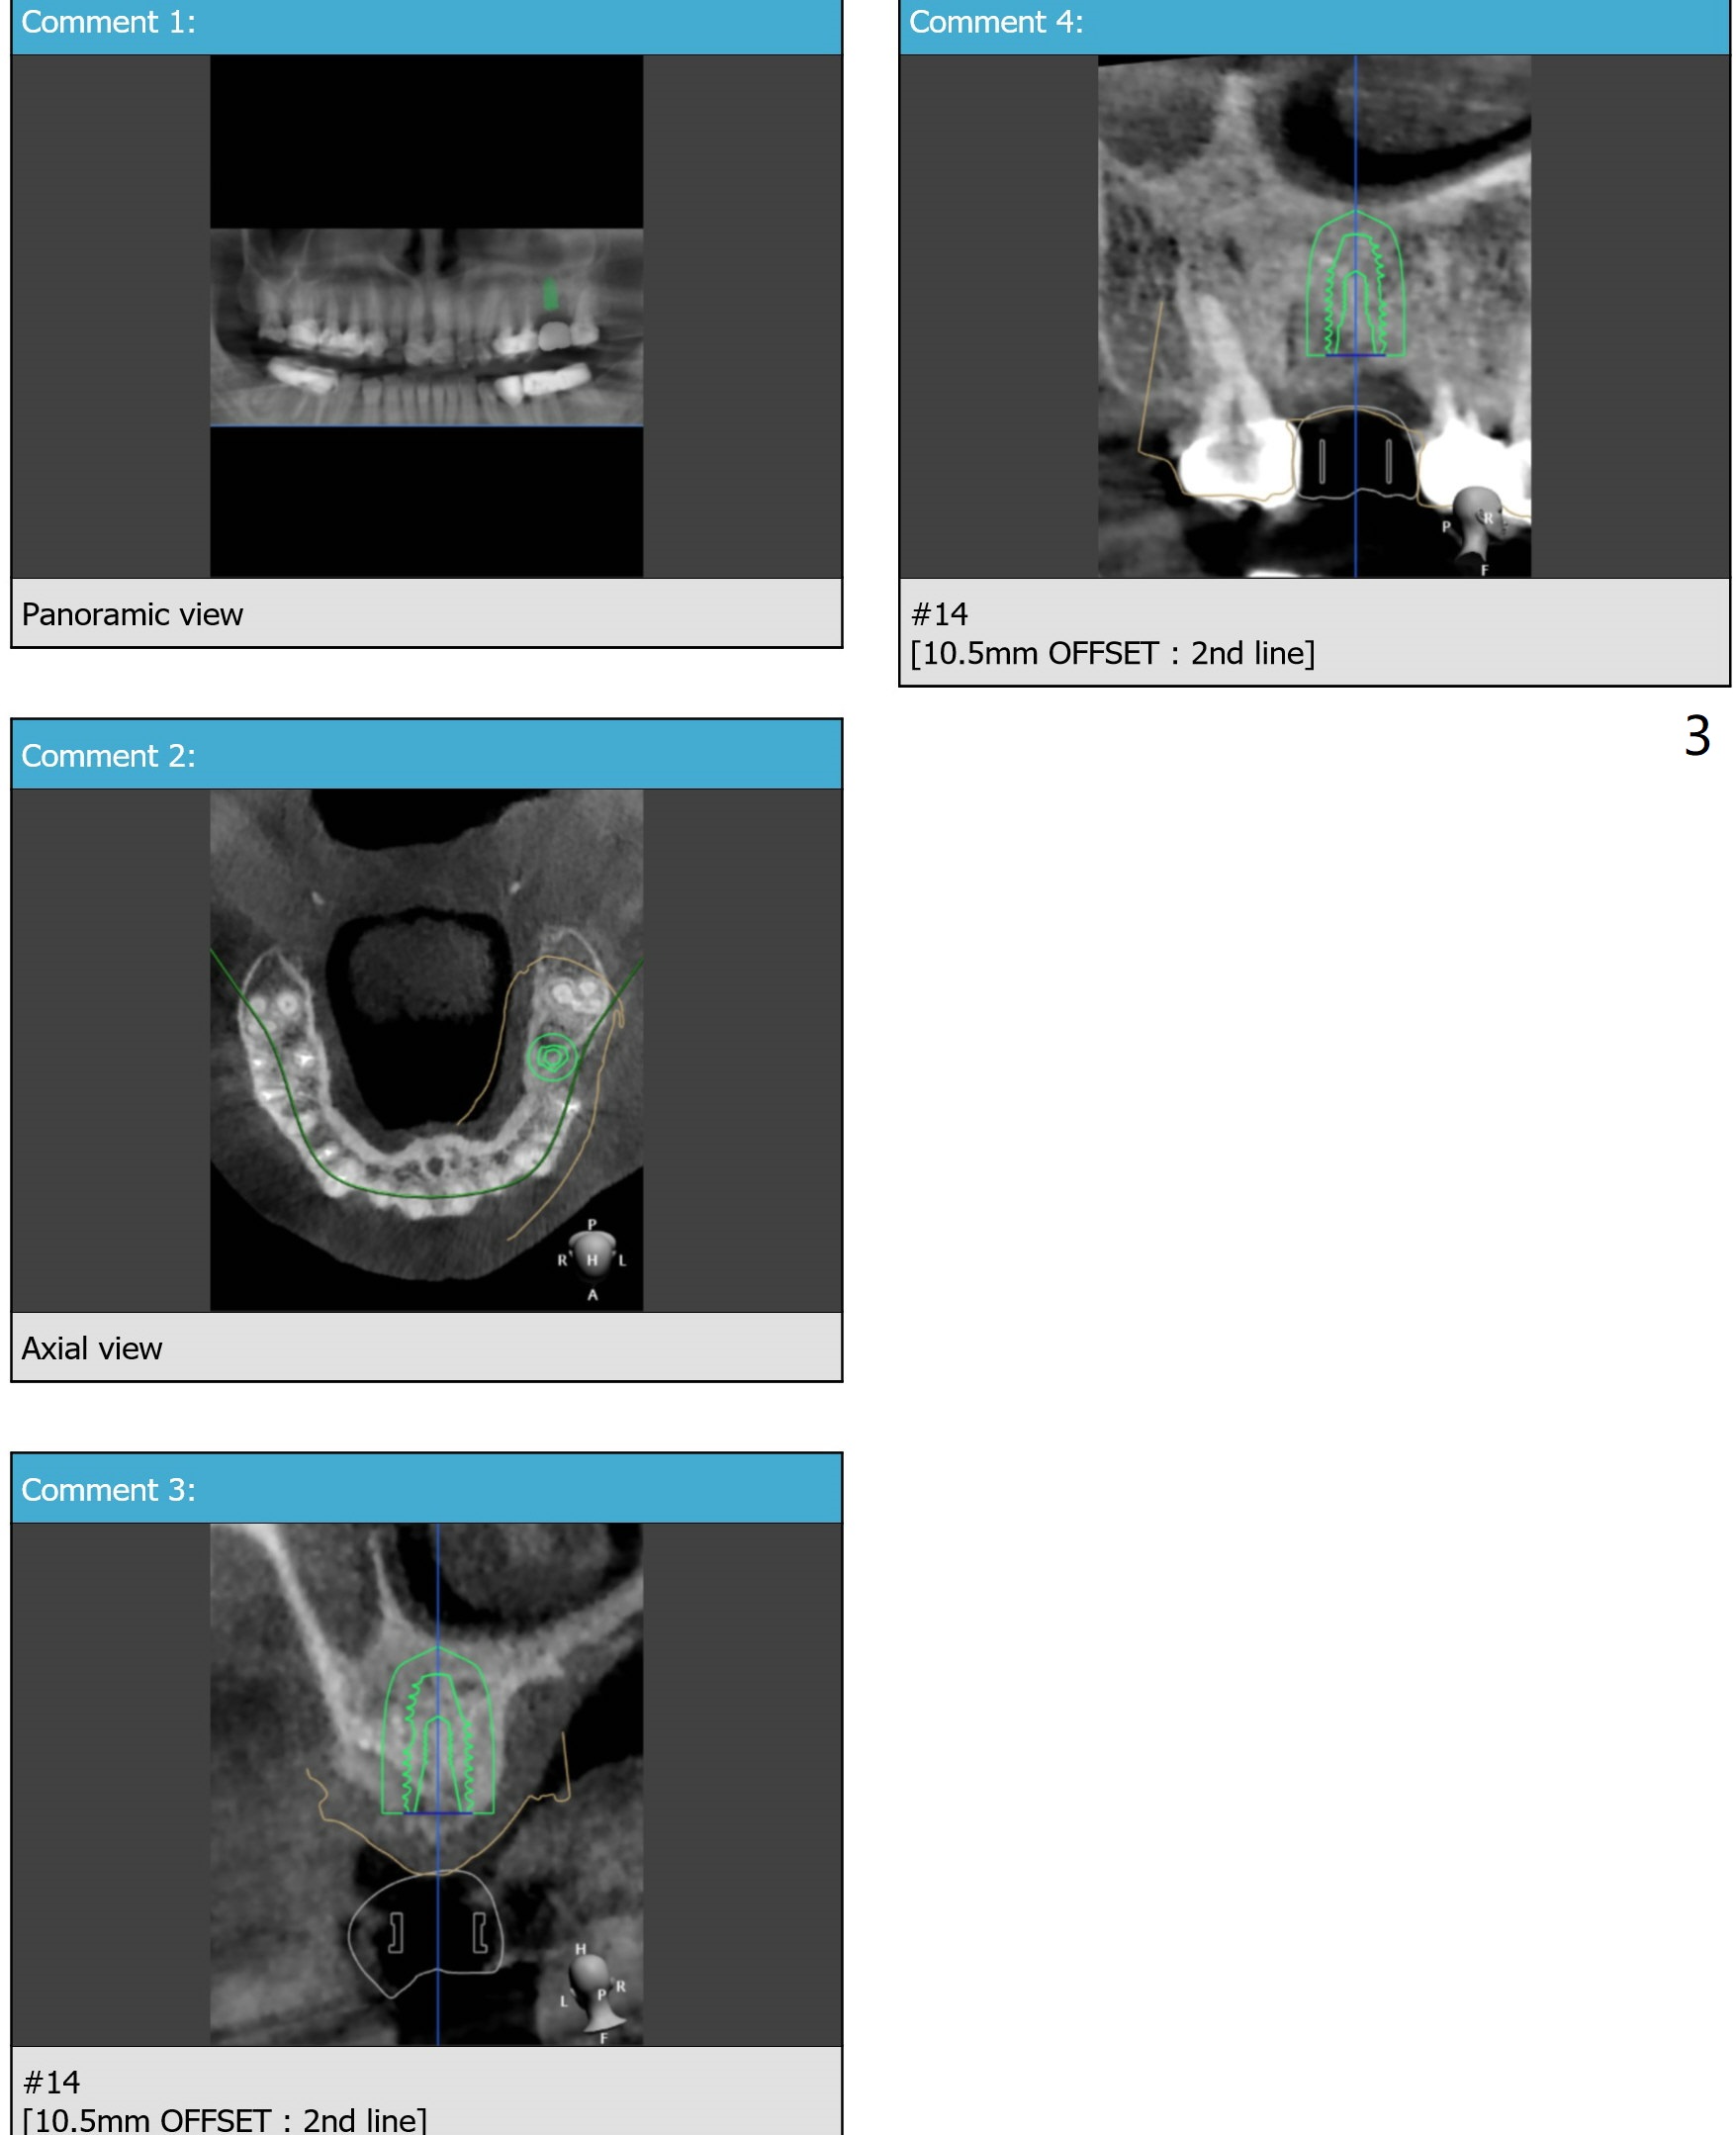

Palatal Placement

Return to Upper Molar Immediate Implant Trajectory II  SP 位点保留后